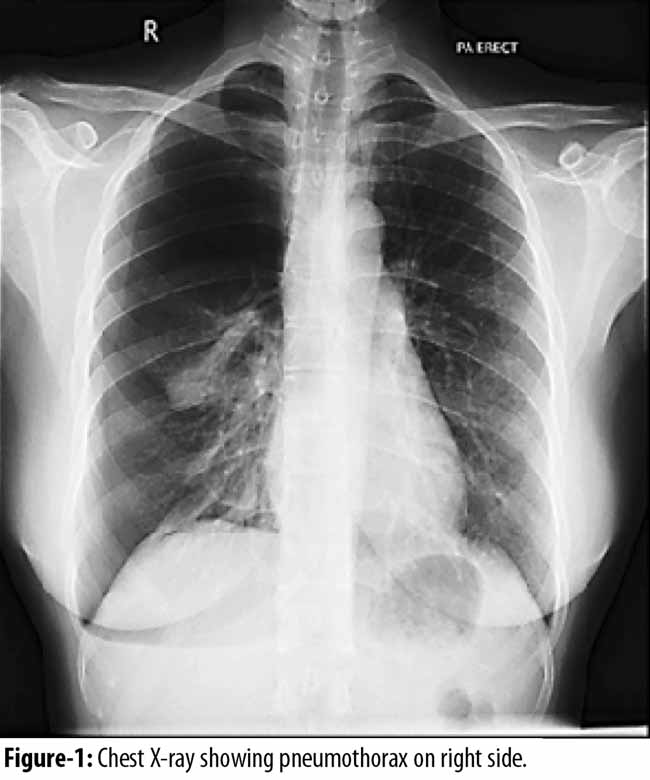

A married woman of 38 years age with two children presented with right sided chest pain, shortness of breath and dry cough. The episode started two days after onset of her menstruation. There was no history of trauma, cough, fever, cigarette smoking or any other chronic lung disease, pelvic or abdominal pain. She was previously in good health, her onset of symptoms coincided with her menstrual period. Chest X-ray revealed right sided pneumothorax with collapsed lung (Figure-1)

CP is an unusual clinical condition; the initial investigation is a Chest X-ray, which can indicate pneumothorax, assisting the physicians to diagnose it. In some cases, pneumoperitoneum might also be associated with pneumothorax, in such cases high resolution computerized axial tomography (CT) scan of chest might be more helpful in providing insight of the condition.

In our case, the patient presented with chest pain, shortness of breath and cough during menstruation, indicating all the classical symptoms of CP. The X-ray revealed a right sided pneumothorax. The patient first went through thoracostomy with some lung physiotherapy and then to stop the recurrence VATS was the procedure of choice, in order to investigate the etiology as well as offer treatment in the form of Pleurodesis. She was kept in observation and then was discharged healthy with no pain.